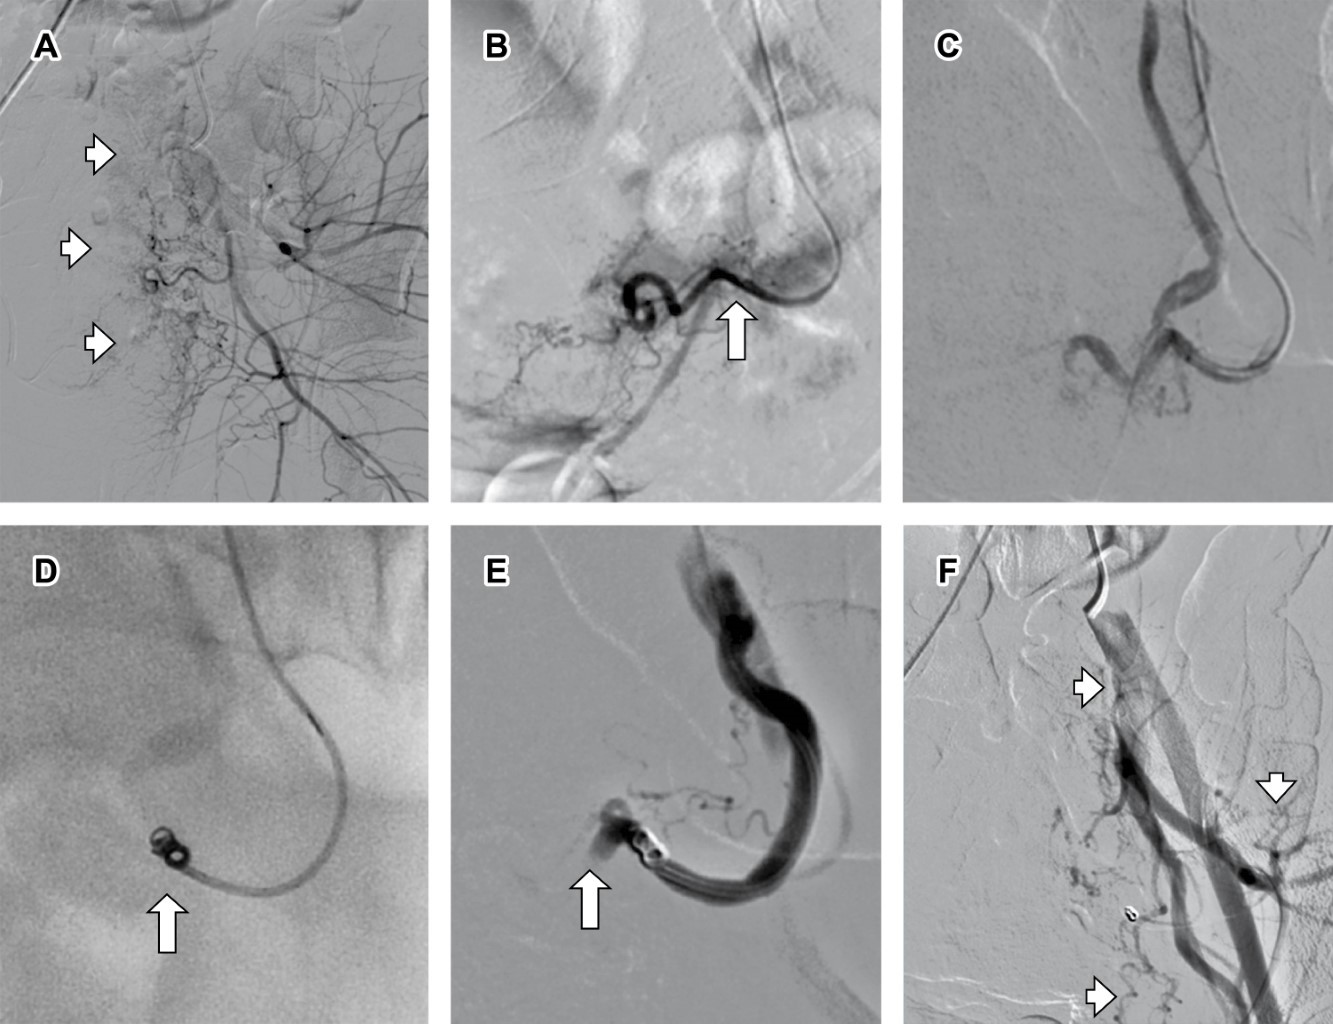

Bajo anestesia general endovenosa y guiada por fluoroscopia, se punciona la arteria femoral común derecha mediante la técnica de Seldinger. Se cateteriza la arteria iliaca interna izquierda con un catéter hidrofílico Cobra de 5 Fr y microcatéter de 2.8 Fr, identificando una arteria uterina tortuosa, con aumento de vascularización y áreas de sangrado activo. Se realiza la embolización con emboesferas de 300-500 micras y un coil de 2 mm × 4 cm en el tronco de la arteria uterina izquierda (Figura 2).

Figura 2